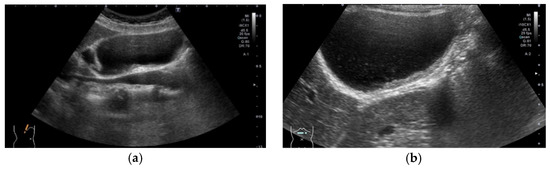

Figure 11. Diffuse GWT without IHL in pancreaticobiliary maljunction (PBM). US showed thickening of the inner hypoechoic layer without the presence of IHL and outermost hyperechoic layer. (a) PBM without biliary dilatation, (b) PBM concomitant with biliary dilatation (*: dilated extrahepatic bile duct).

Pancreaticobiliary maljunction (PBM) is a congenital anomaly defined as a junction of the pancreatic and bile ducts located outside the duodenal wall and a risk factor for GBC development via the hyperplasia–dysplasia–carcinoma sequence. The incidence of mucosal hyperplasia of PBM patients without biliary dilatation was reported to be 72% [63] to 91% [64]. The GB wall appeared as thickening of the inner hypoechoic layer without IHL and outermost hyperechoic layer (Figure 11). Histologically, the GB of PBM without biliary dilatation showed wall thickness composed of epithelial hyperplasia (88%), hypertrophic muscular layer (63%), and subserosal fibrosis (88%) [65].